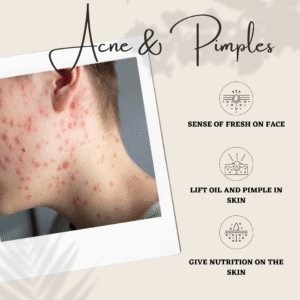

ACNE & PIMPLES

ACNE & PIMPLES

Clear Skin Solution: Acne & Pimples |Trusted Treatment